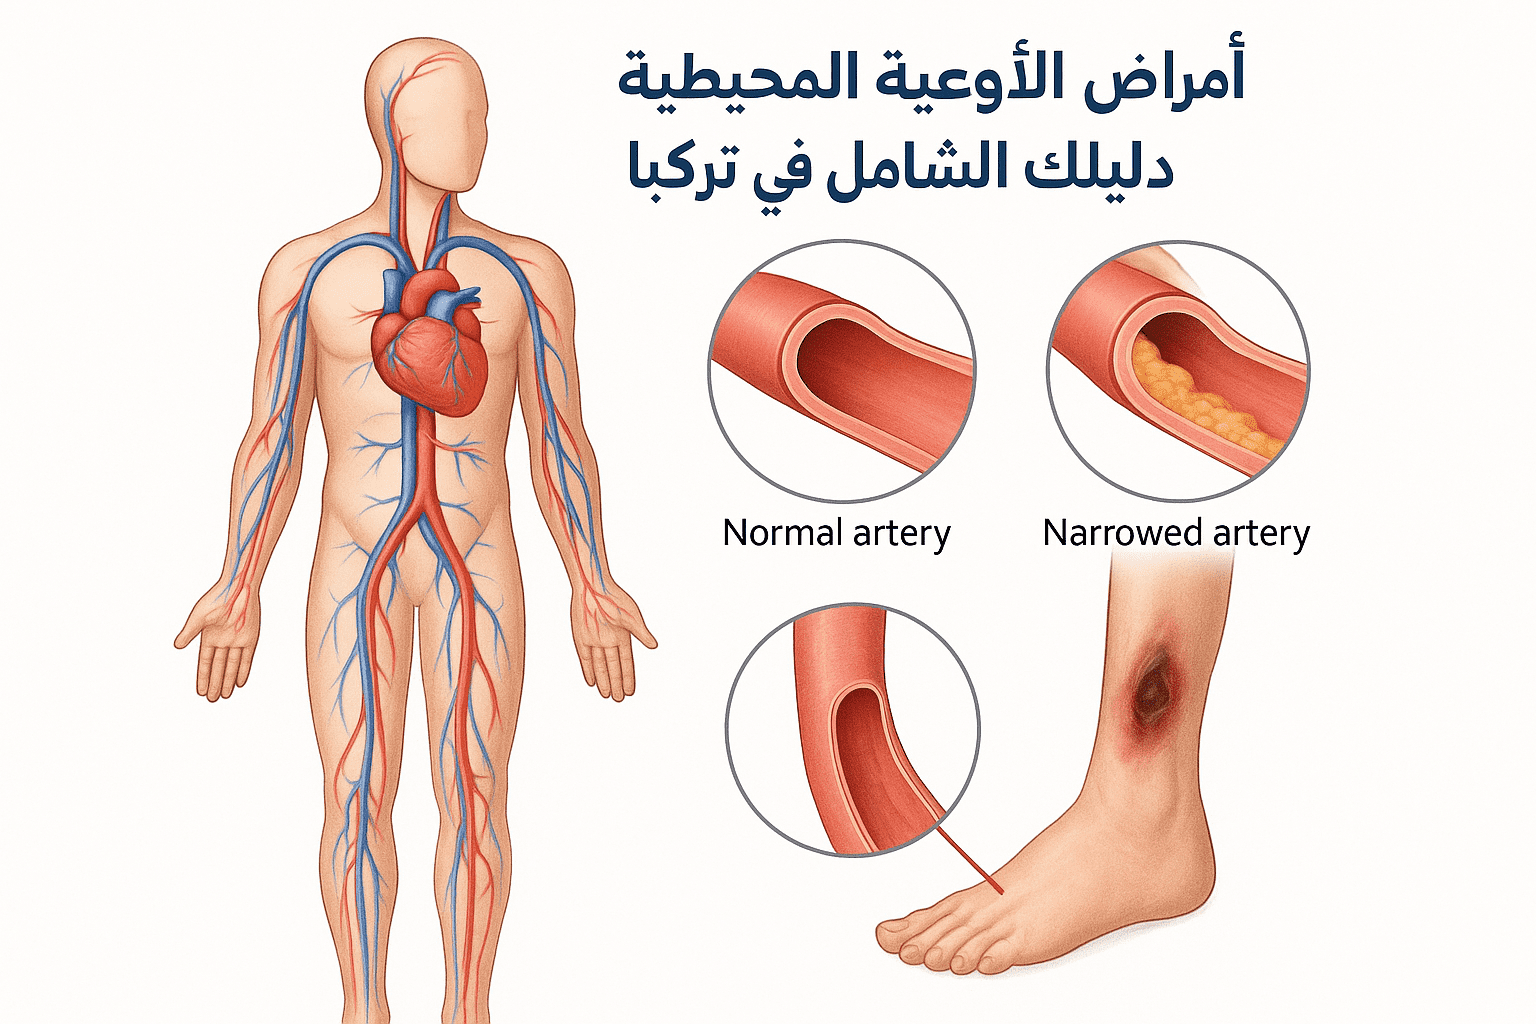

مقالات طبية من مساهمات الأطباء